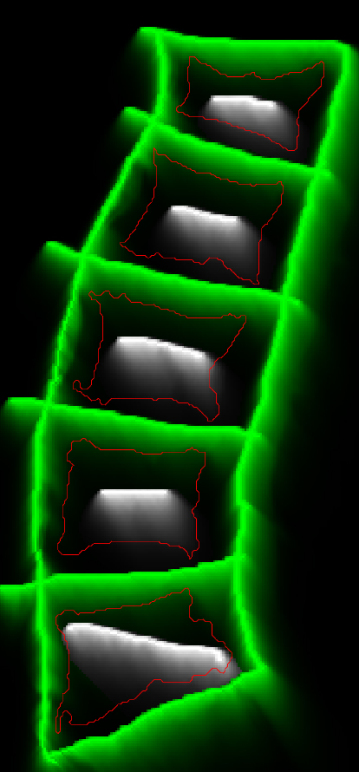

The balance induced by the weights produces smoother borders at regions with small pixel intensities. Moreover, as long as the interior annotation contains small portions of the dark and bright regions, it can work well even with rough interior and exterior seed points. To better illustrate this, Figure 3 shows a few iterations of BGrowth for a single vertebral body segmentation. Note that, at iteration 5, a few dark regions (outside of the vertebral body) are still part of the foreground and, as the balancing goes on, the foreground shrinks towards the ground-truth. The final result is quite close to the manual segmentation. Figure 4 shows another example of BGrowth’s iterations on five lumbar vertebrae. Note that, the method works quite well even when a simple line is given as seed points. The only constraint is that the interior annotation has to comprise the dark/bright regions within the vertebral body.

![]() |

| Annotations | Iteration 1 | Iteration 5 |

| Iteration 10 | Iteration 20 | Iteration 50 |

As we work with the balance of old and new strength factors, it might happen that the process of expansion goes back and forth on the same pixel. Therefore, we would recommend the definition of a maximum number of iterations depending on the kind of image being segmented. We have empirically used a maximum of 30 iterations for the segmentation of a single vertebral body. For a whole exam, as exemplified in Figure 4, a few more iterations might be necessary.